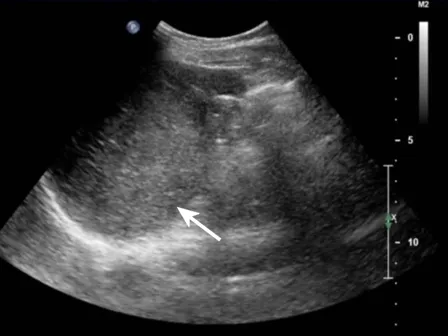

灰阶超声显示脾内多个低回声团块,呈分叶状,形态不规则(箭头所示)。